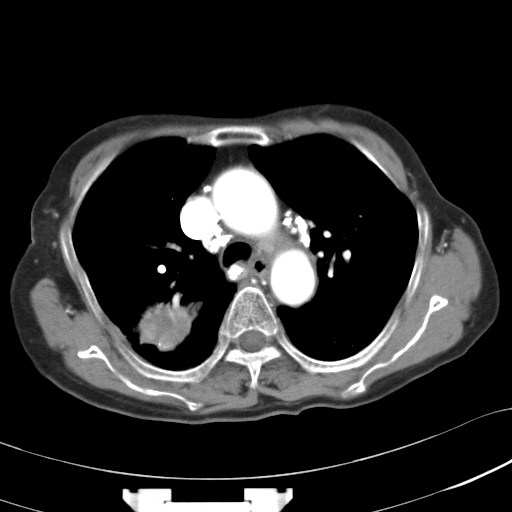

以下是引用liuyue在2007-3-2 17:15:00的发言:[br]1位置:右上叶后段[br]2性质:大分叶、粗长毛刺、条状斑片状钙化、纵隔多发淋巴结钙化,无强化,故考虑:肺结核灶(陈旧)